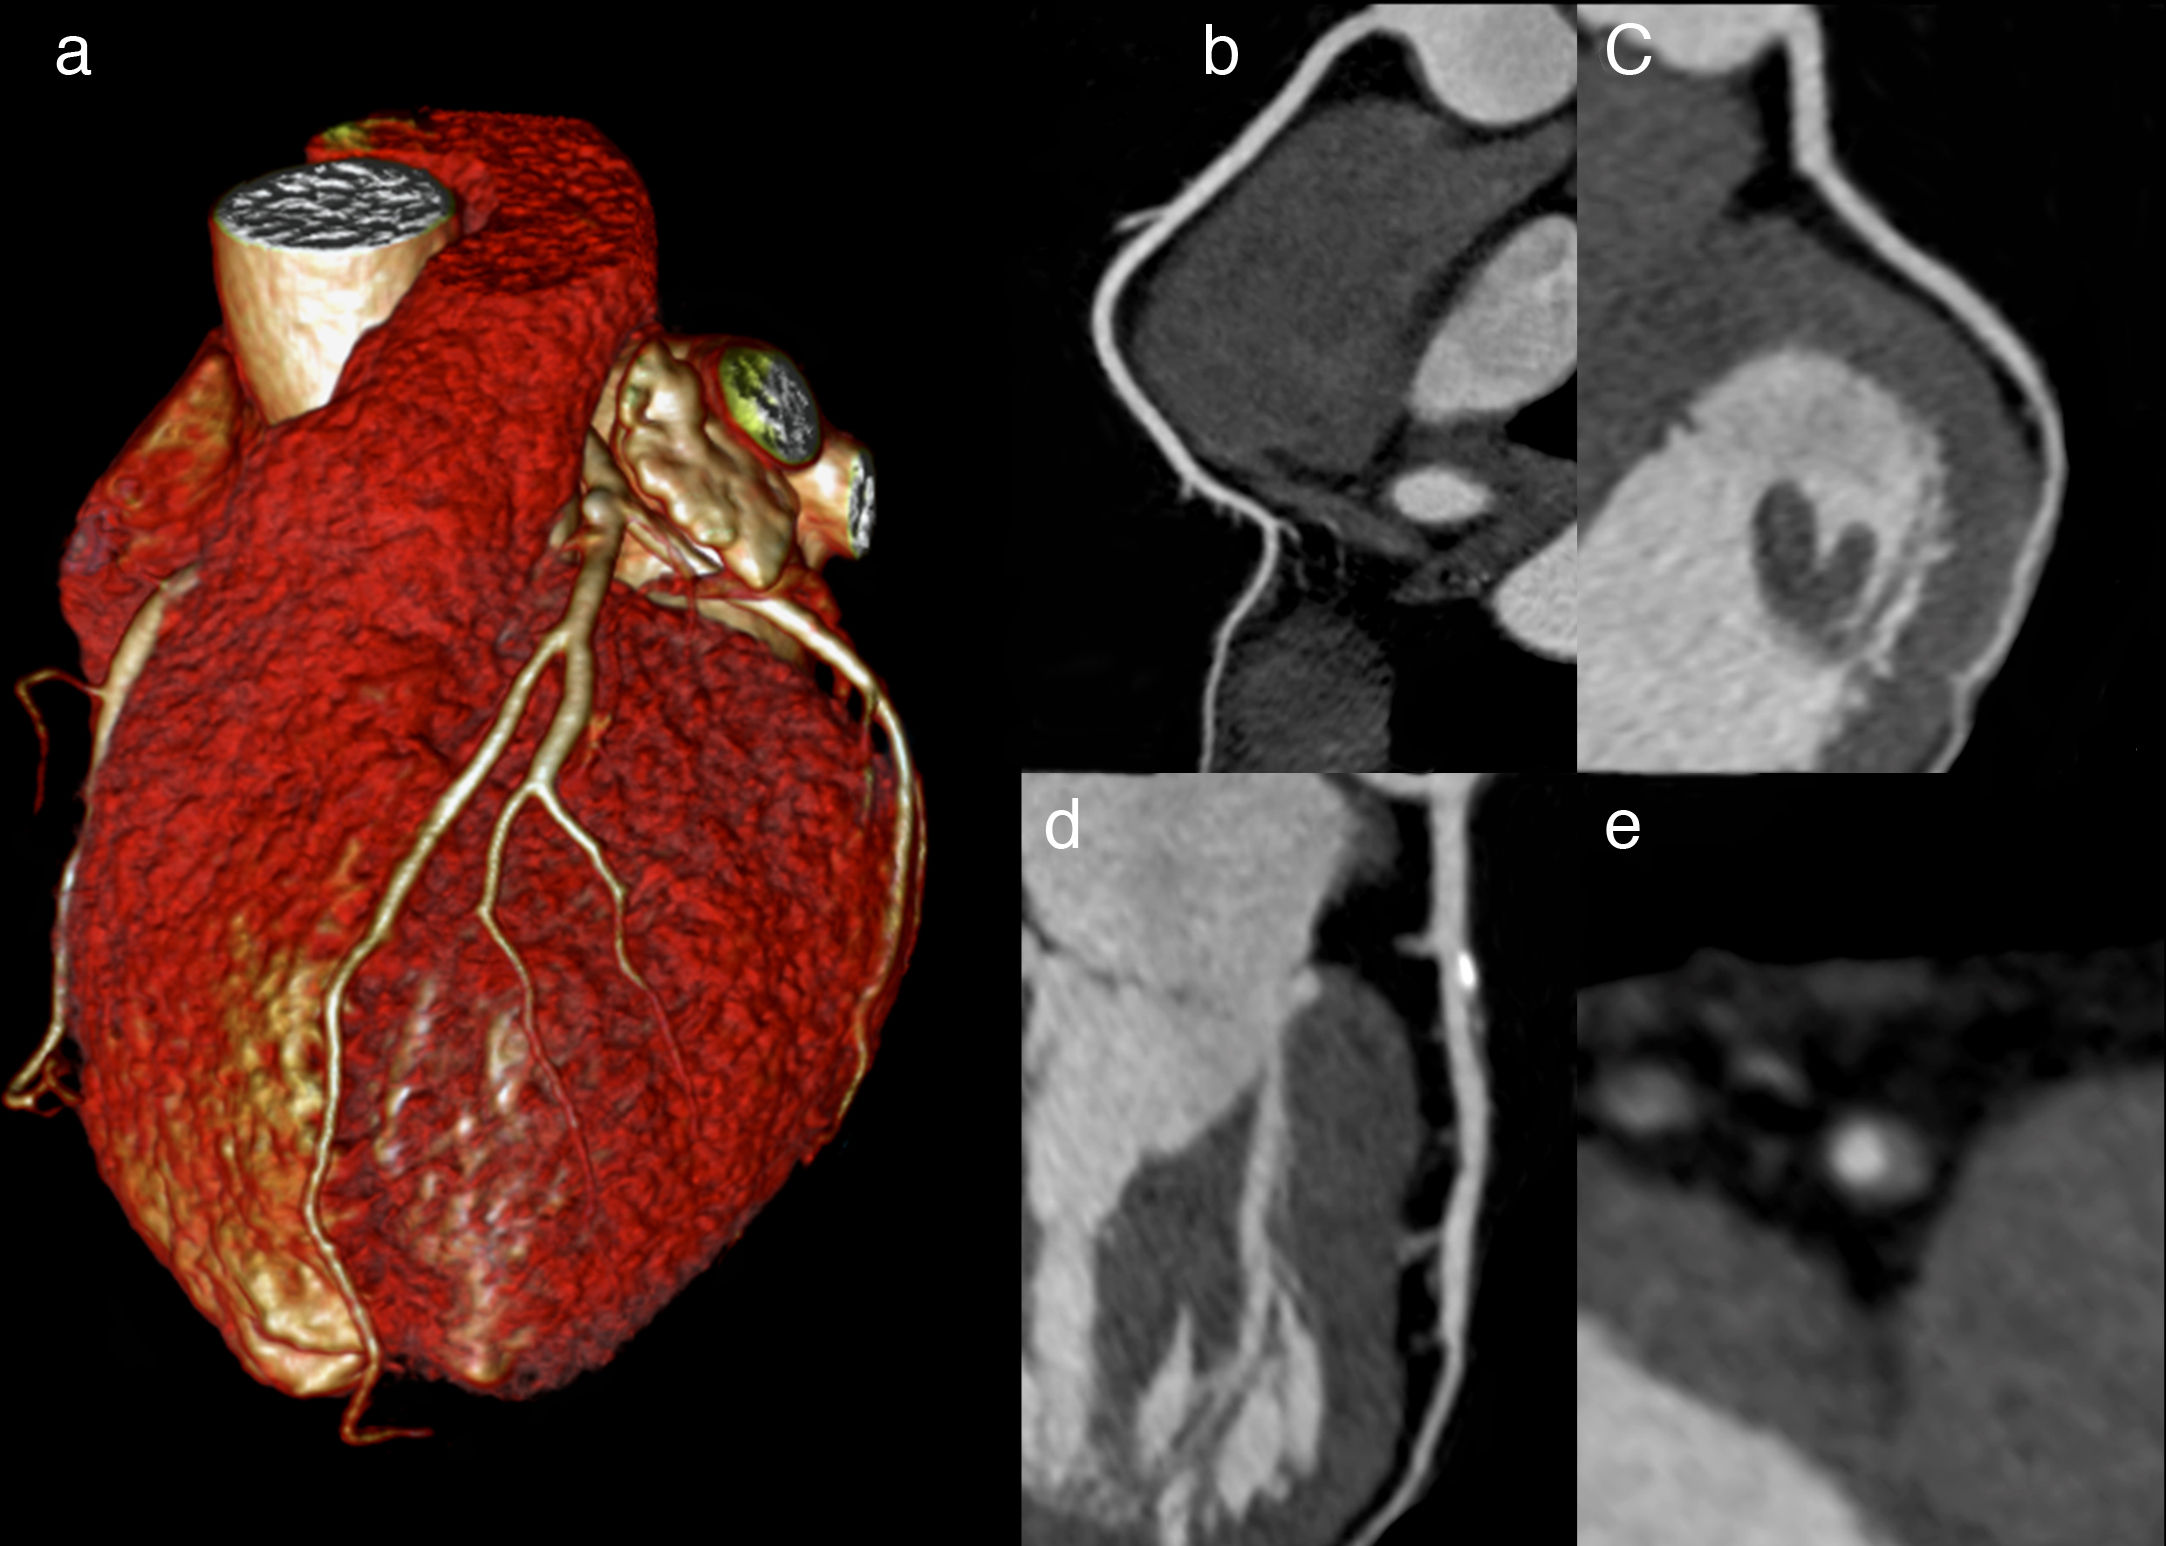

Tomografía computada versus angiografía invasiva en la angina de pecho estable

28 abril 2022

En los pacientes remitidos para cateterismo coronario por dolor torácico estable y con probabilidad intermedia de enfermedad coronaria antes de la prueba, la evaluación inicial por tomografía computada tuvo un riesgo de eventos cardiovasculares mayores similar a los de la evaluación invasiva, pero una menor frecuencia de complicaciones mayores relacionadas con el procedimiento. New England Journal of Medicine, 28 de abril de 2022.